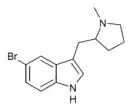

5-Br-MPMI | 5-bromo-3-[(1-methylpyrrolidin-2-yl)methyl]-1H-indole | 143322-57-0 |

|